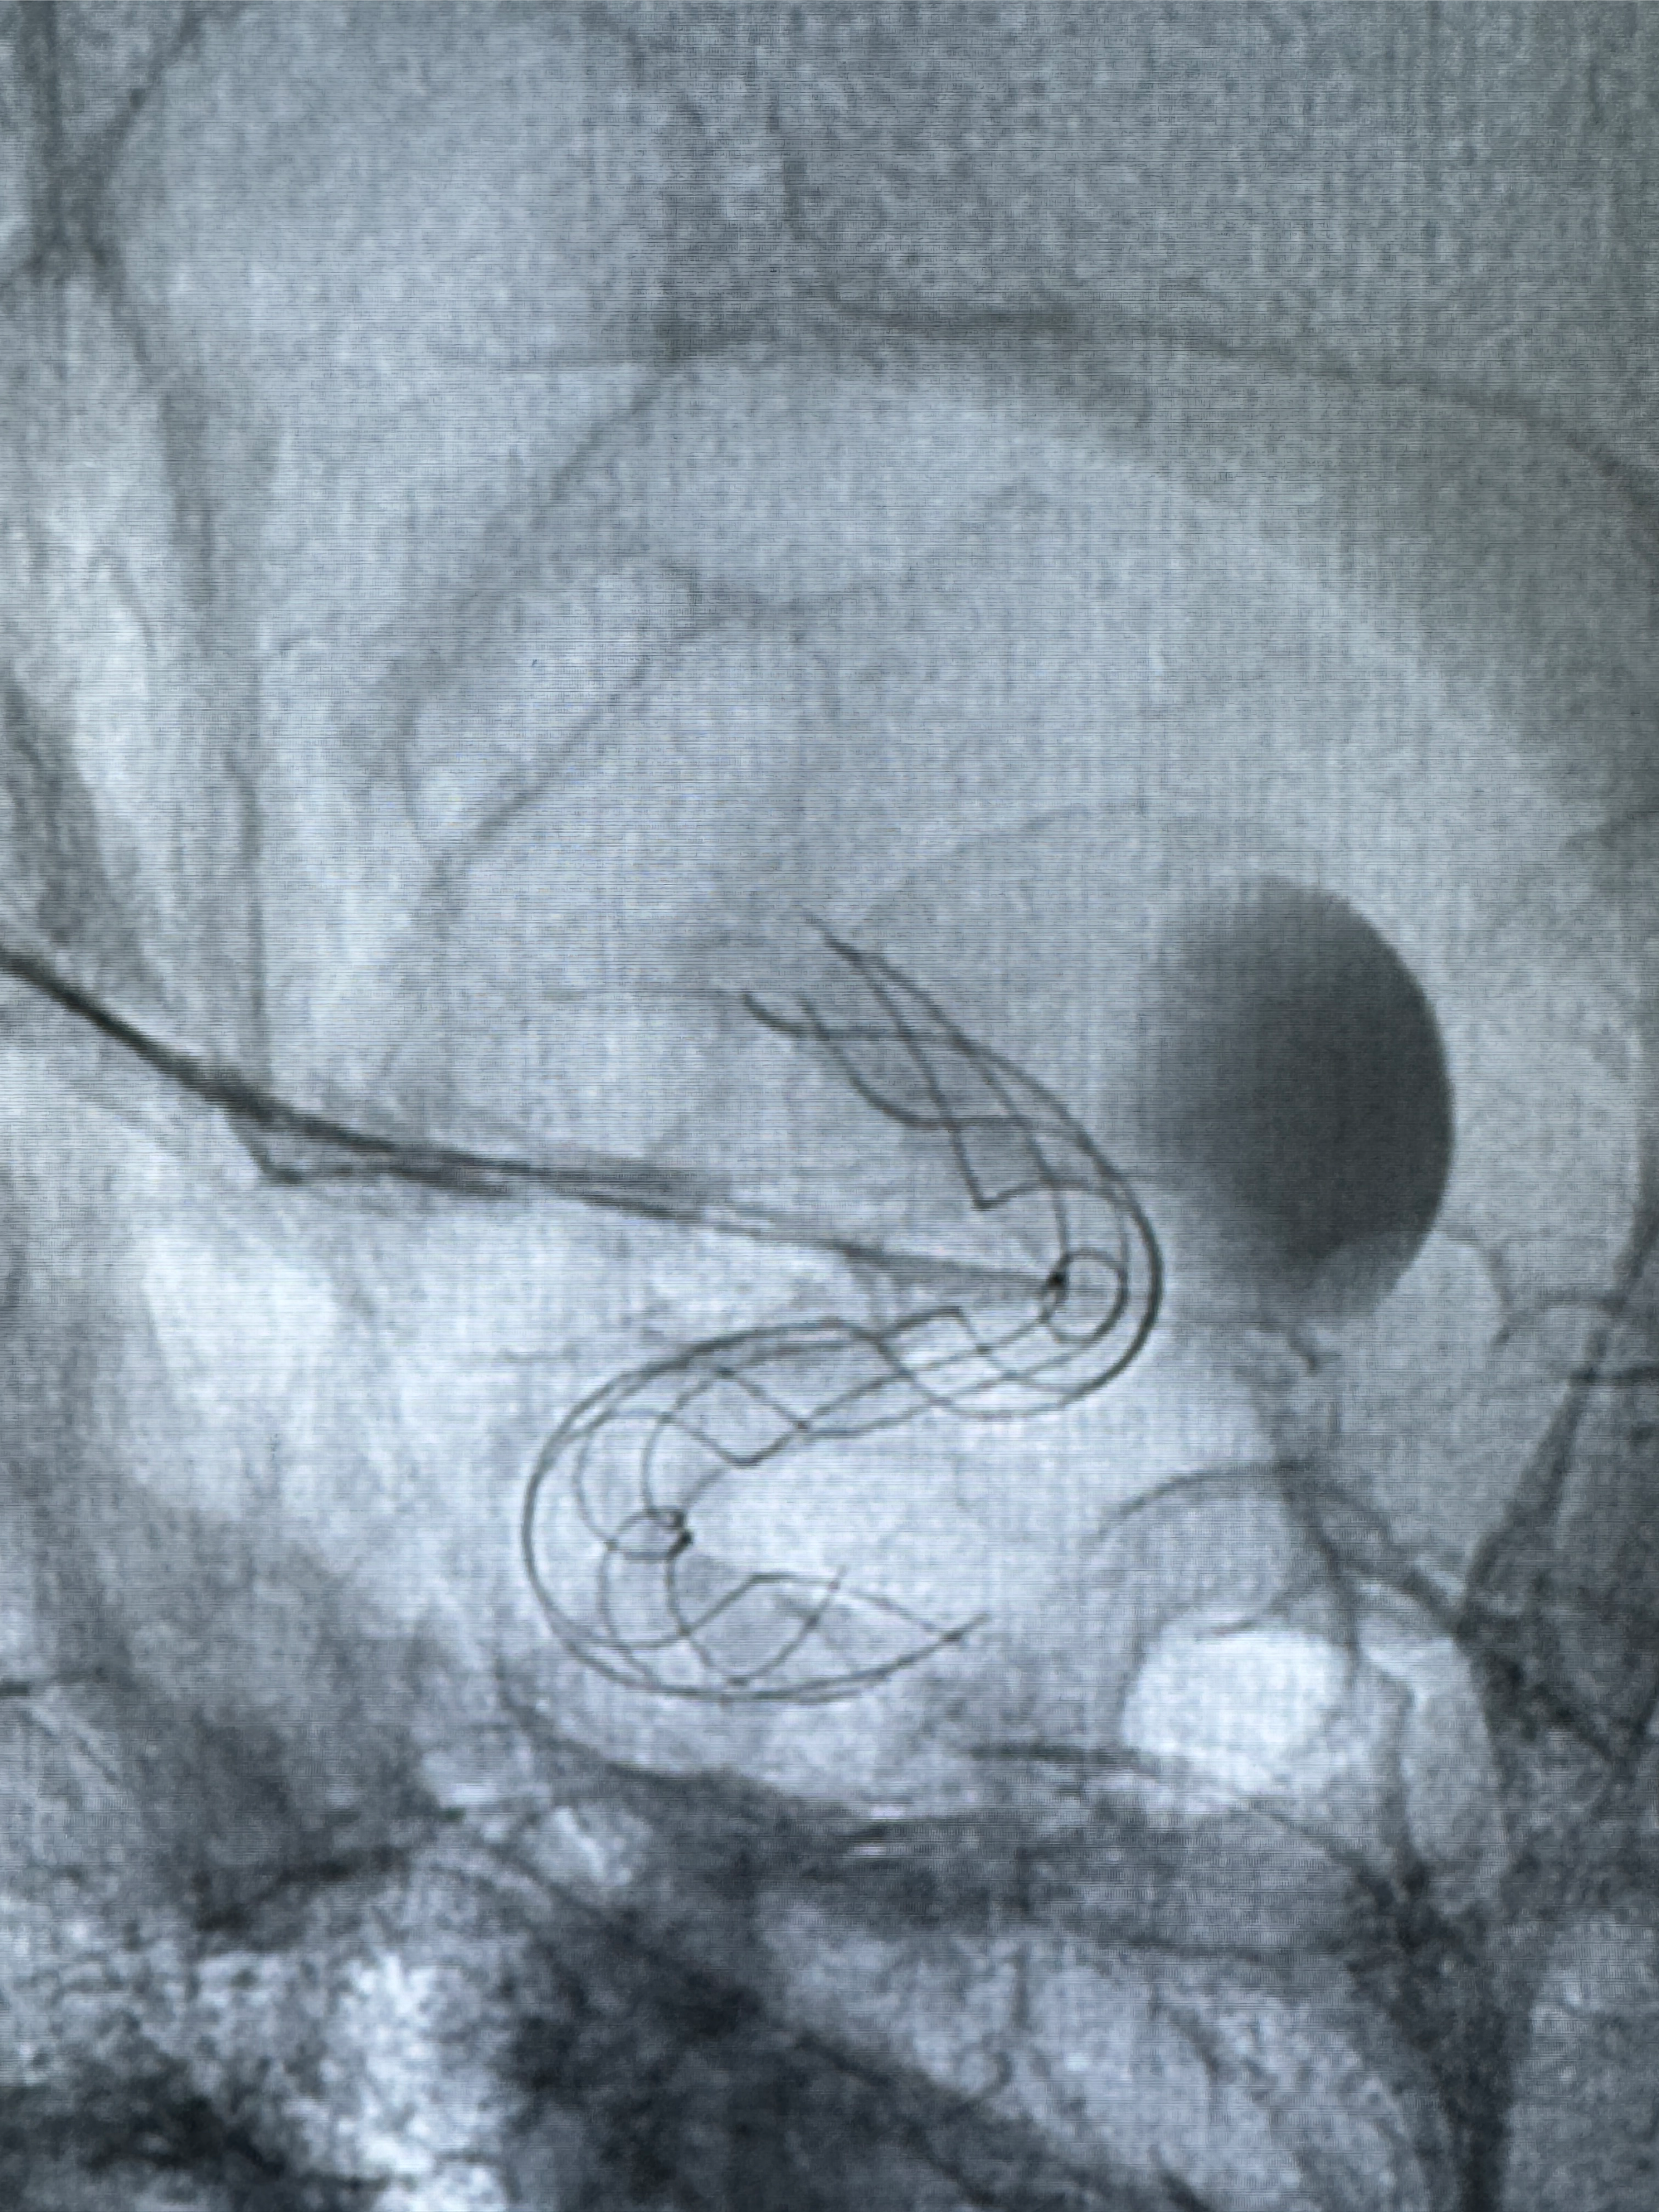

透视可见红圈部分为支架导管的头端

手推冒烟显示支架位置及展开情况,箭头为支架导管的位置

尝试回收支架失败,只能考虑释放支架了

逐帧图像展示歪着脖子释放支架,旁边吩咐助手手机摄影、拍照留像(透视机不能留影像)

接下的视频为释放支架的过程及试图确认支架与血管的关系